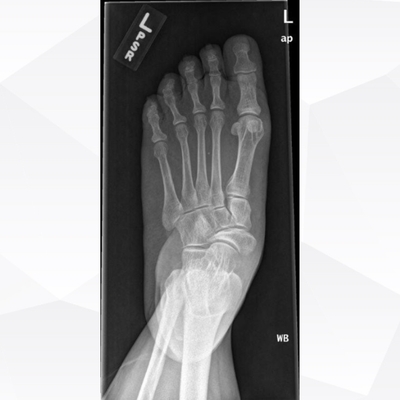

Click on an image below to view more info.